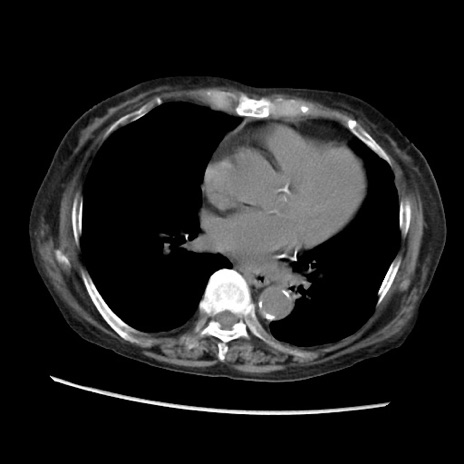

症例31(横断像)

【症例】80歳代 女性

【主訴】腹部膨満感

【現病歴】他院にて肝硬変にてフォロー中。1週間前から便秘、腹部膨満感、臍部腫瘤あり受診となる。

【既往歴】肝硬変

【身体所見】腹部膨隆あり、皮膚変化なし、疼痛なし。

【データ】WBC 4600、CRP 0.25